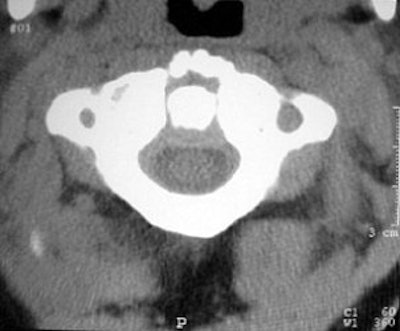

![]() |

| Image G |

The 0.5-mm slices offer fine bone detail, but pay a price on the soft-tissue images in terms of soft-tissue differentiation. Whereas the thicker (5-mm) slices fail to show the bone detail of the fracture well, but possess greater contrast resolution on the soft-tissue window to differentiate spinal cord from surrounding spinal fluid.